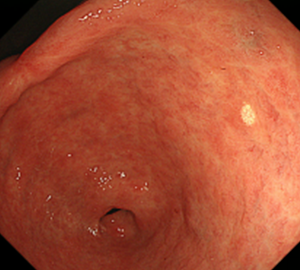

瀑 ばく 状胃の内視鏡検査 : 宇野コラム Uno column。